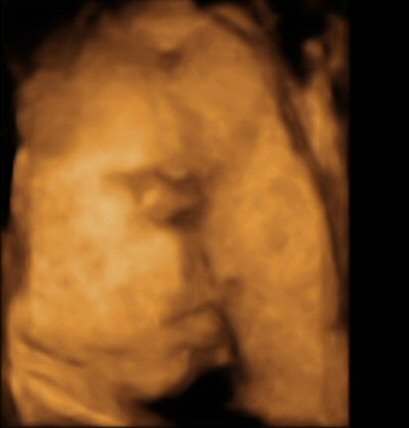

- 29 week 4D scan

- The scan photos shown below are 3D images from the babybond 4D scan at 29 weeks gestation.